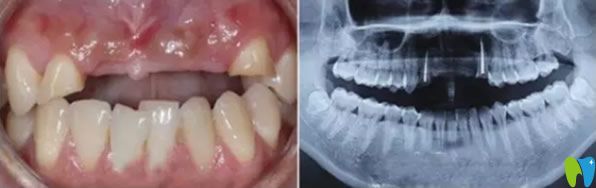

一次意外導(dǎo)致老公門牙缺失,在一家小診所做的烤瓷牙,這幾年用著還可以,但是前幾天發(fā)現(xiàn)牙齦萎縮很嚴(yán)重 ,明顯一個坑。三十出頭小伙子看著像四十多歲大叔,這可怎么辦?網(wǎng)上說牙齒缺失可以通過種植牙來修復(fù),我們也不知道有沒有年齡限制,老公都30多歲了還能做種植牙?成都瑞爾口腔在我們這的口碑挺不錯的,我就陪老公來咨詢。

來院后面診的是郝亦工醫(yī)生,詳細(xì)檢查后,說老公的門牙可以通過牙齒種植來修復(fù),同時也能改善牙齦萎縮的現(xiàn)狀。郝主任說種植牙沒有年齡限制,只要身體無疾病,都可以種植。

郝醫(yī)生通過醫(yī)學(xué)種植技術(shù),根據(jù)老公牙齒狀況設(shè)計種植方案。他將種植體與人體兼容性高的鈦金屬精準(zhǔn)植入缺牙區(qū)的牙槽骨內(nèi),等三個月后,人工牙和牙槽骨緊密結(jié)合,再做烤瓷牙、全瓷牙冠。郝醫(yī)生植入牙根手術(shù)完成后,老公從手術(shù)室出來牙齦看著就沒有之前那么憋了,飽滿了許多。